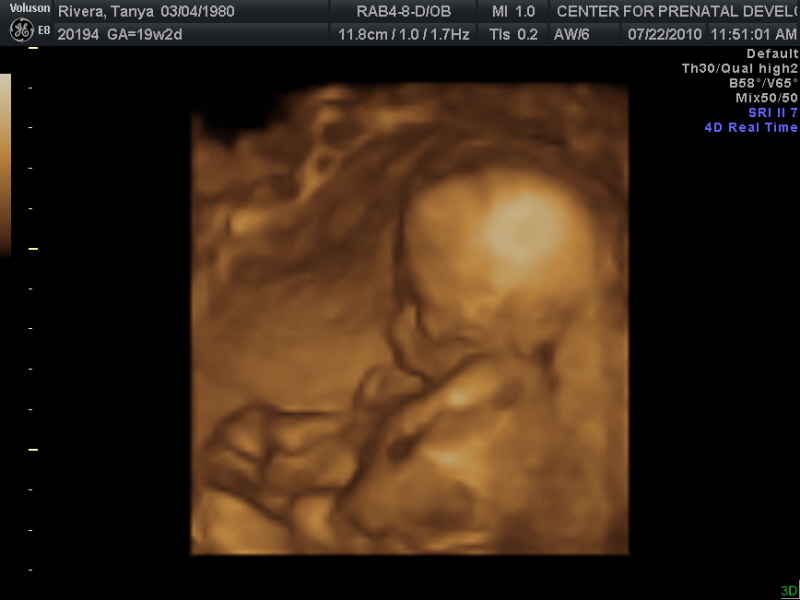

First of all...we are expecting our second child in Dec. My due date is Dec.14, 2010 and it's a BOY!! We are just so excited!!! Vivian is too, but I think she wanted a little sister. She still keeps asking me "I not having a sis-toe?" (how she says sister) I know she is just excited for a sibling, she is always telling me all the things she wants to teach, show, and share with her "brother" she wants to swing him, hold his hand, show him bugs...the list goes on each day!! Here are some pictures of our lil man

He is just chillin...we couldn't get him to move very much, and even asked the tech to try ONE MORE TIME to get a face shot, but it didn't work...

Still just laying on his side...